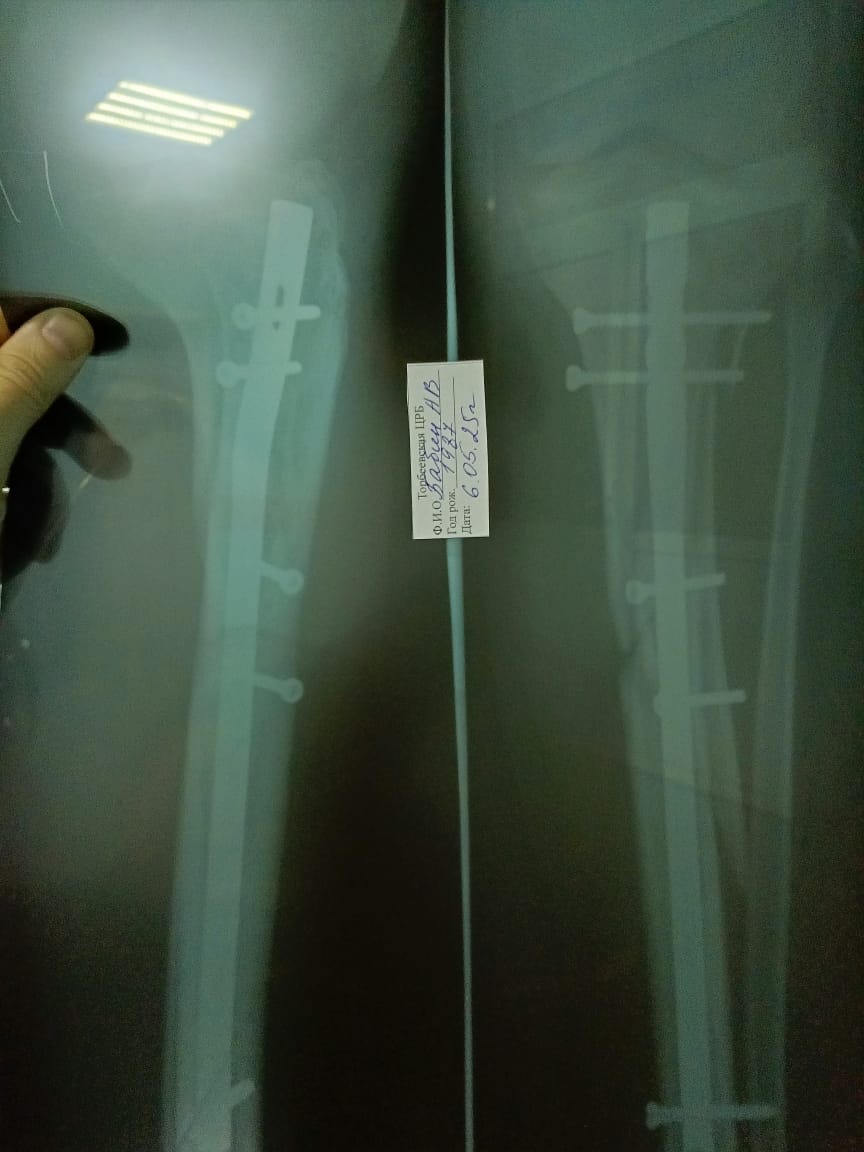

Правильно ли собрали берцовые кости   1 ответ

На сколько критично результат по снимкам. За какое время срастeтся кость. Какие рекомендации и упражнения можете порекомендовать.